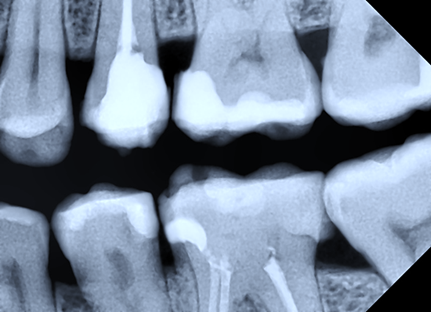

The proximal morphology of the restorations was evaluated by assessing the emergence profile categorized as concave, convex, or straight surface. Similarly, the cervical marginal adaptation of the restoration was studied by evaluating the presence of a harmonious transition between tooth and restoration or a visible radiographic overhang (Fig. 1), with the calculation of its size.

|

Fig. 1 Bitewing radiography. Distal restoration in tooth 45 with the presence of overhang. Note: Red line – overhang. |